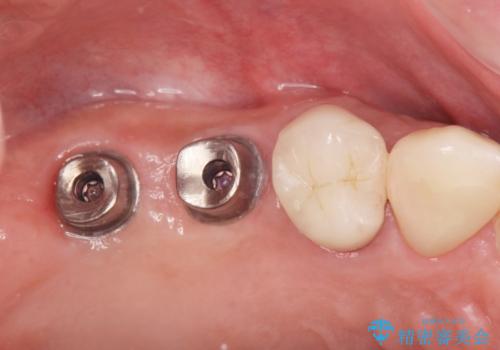

より清掃性の高い、チタン製カスタムアバットメント、審美製・強度に優れるジルコニアインプラントを用いたインプラント治療を計画します。

- 88万円(インプラント×2・チタンカスタムアバットメント×2・ジルコニアクラウン×2・仮歯×2)費用は治療当時の料金となります